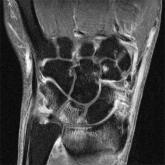

MRI detects high level of subclinical small joint inflammation

- Author:

- Sara Freeman